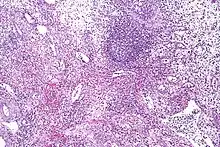

| Eosinophilic cystitis showing edematous and chronically inflamed lamina propria with numerous eosinophils. | |

Cystoscopy typically reveals large mucosal edema along with erythematous, polypoid, velvety red lesions. It can be mistaken for vesical rhabdomyosarcoma in children.[25] Eosinophilic cystitis is hard to differentiate from other cystitis types (like interstitial and tuberculous cystitis), neoplastic lesions (like carcinoma in situ), and other bladder cancers. Therefore, in order to confirm the diagnosis of eosinophilic cystitis, biopsies are required.[2] Transmural inflammation is present histologically, primarily with eosinophils. The lamina propria has more severe edema and inflammation. A contracted bladder may result from focal muscle necrosis and varying degrees of detrusor muscle fibrosis.[26]